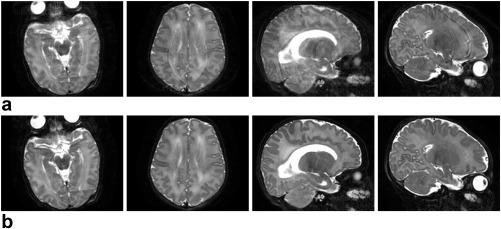

The method alternates between motion estimation and reconstruction using a common objective function for both. Estimates of three-dimensional motion states for each shot and slice are gradually refined by improving on the fit of current reconstructions to the partial k-space information from multiple coils. Overlapped slices and super-resolution allow recovery of through-plane motion and outlier rejection discards artifacted shots. The method is applied to T and T brain scans acquired in different views.

The procedure has greatly diminished artifacts in a database of 1883 neonatal image volumes, as assessed by image quality metrics and visual inspection. Examples showing the ability to correct for motion and robustness against damaged shots are provided. Combination of motion corrected reconstructions for different views has shown further artifact suppression and resolution recovery.

该程序大大减少了 1883 个新生儿图像体积数据库中的伪影,通过图像质量指标和视觉检查进行评估。提供了示例,展示了校正运动和对损坏拍摄具有鲁棒性的能力。对不同视图的运动校正重建进行组合,进一步显示出对伪影的抑制和分辨率的恢复。